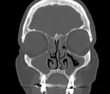

Rinosinusite

Infiammazione del naso e dei seni paranasali con accumulo di secrezioni e muco infiammatorio. Si può manifestare con ostruzione respiratoria nasale persistente, rinorrea e in alcuni casi dolore facciale in regione frontale e zigomatica, con un forte impatto sulla vita quotidiana. Può associarsi a poliposi nasale. Nelle forme croniche può essere indicata una TAC dei seni paranasali per un migliore inquadramento. Il trattamento è medico nelle forme più lieve, mentre i quadri più importanti e cronici possono richiedere un intervento di chirurgia endoscopica nasale.